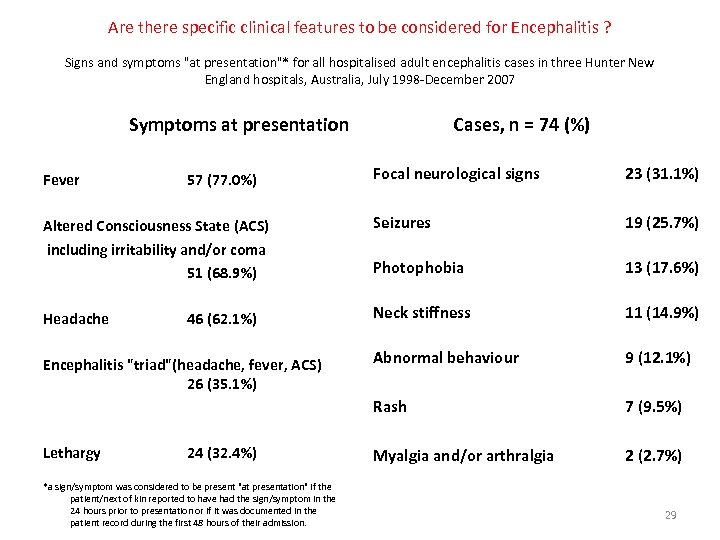

Are there specific clinical features to be considered for Encephalitis ? Signs and symptoms "at presentation"* for all hospitalised adult encephalitis cases in three Hunter New England hospitals, Australia, July 1998 -December 2007 Symptoms at presentation Cases, n = 74 (%) Focal neurological signs 23 (31. 1%) Altered Consciousness State (ACS) including irritability and/or coma 51 (68. 9%) Seizures 19 (25. 7%) Photophobia 13 (17. 6%) Headache Neck stiffness 11 (14. 9%) Abnormal behaviour 9 (12. 1%) Rash 7 (9. 5%) Myalgia and/or arthralgia 2 (2. 7%) Fever 57 (77. 0%) 46 (62. 1%) Encephalitis "triad"(headache, fever, ACS) 26 (35. 1%) Lethargy 24 (32. 4%) *a sign/symptom was considered to be present "at presentation" if the patient/next of kin reported to have had the sign/symptom in the 24 hours prior to presentation or if it was documented in the patient record during the first 48 hours of their admission. 29